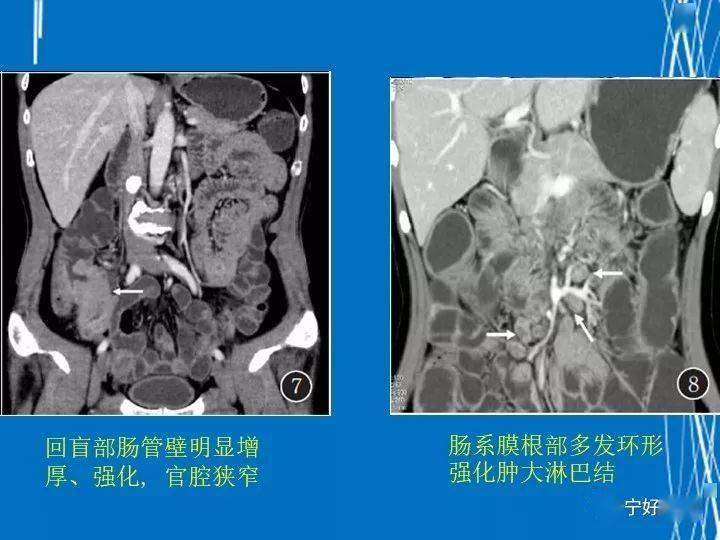

而且,这病还特别喜欢在肠道的一些关键部位“安营扎寨”,比如回肠和结肠的交界处。这些地方一旦被它盯上,那可真是麻烦大了。X光片上,这些地方的线条变得特别扭曲,有时候还能看到一些像小袋子一样的东西,这些都是克罗恩病引起的肠道。